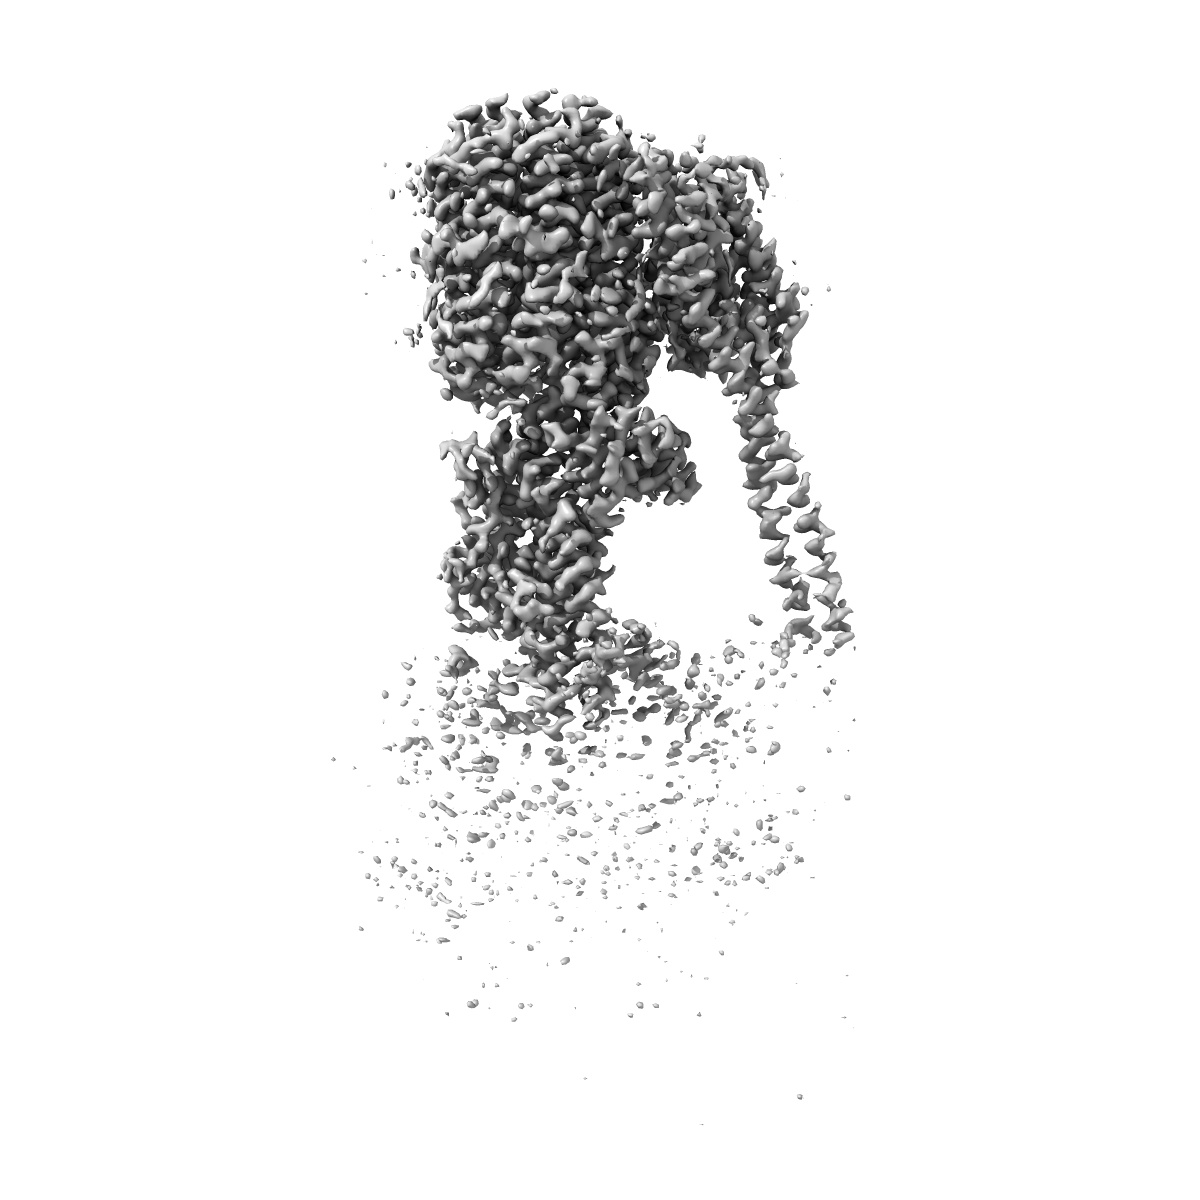

Cryo-EM structure of Mycobacterium tuberculosis ATP synthase Fo in complex with bedaquiline(BDQ)

Single-particle2.85 Å

Sample: Mycobacterium tuberculosis ATP synthase Fo with bedaquiline(BDQ)